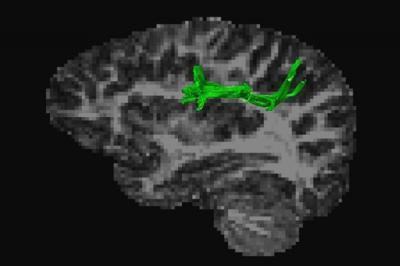

The 'arcuate fasciculus anterior' (green) is a neural pathway that connects brain regions in the frontal and parietal lobes often used for arithmetic. The pathway is sheathed in myelin, or 'white matter'. The researchers found a positive correlation between the tract's white matter quality and proficiency in adding and multiplying.

(Photo Credit: © Leen Van Beek)

"We found that a better quality of the arcuate fasciculus anterior – a white matter tract that connects brain regions often used for arithmetic – corresponds to better performance in adding and multiplying, while there is no correlation for subtracting and dividing."